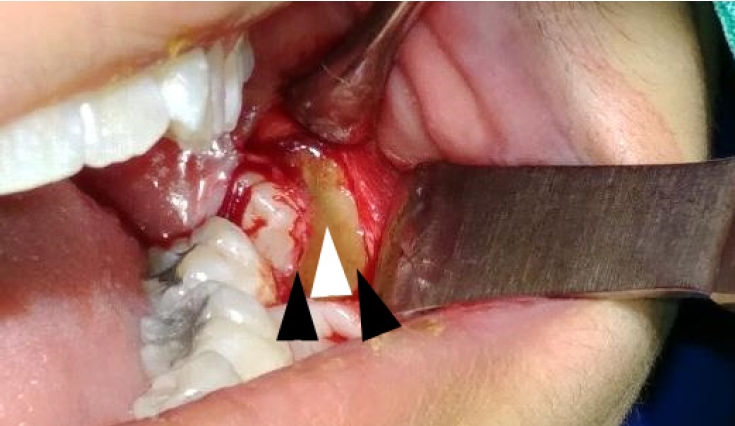

Intraoperatively, alternating bands of blue-gray and yellow discoloration of the alveolar bone was noted around both #38 and #48. (Fig. 2 and 3) No discoloration of adjacent teeth was observed. The overlying mucosa showed no discoloration or textural changes. During alveolar bone reduction, the bone density and quality appeared normal, and no other abnormal signs or symptoms were present.

Alternating bands of blue-gray and yellow discoloration of the alveolar bone observed during flap reflection for surgical extraction of the left mandibular impacted third molar.